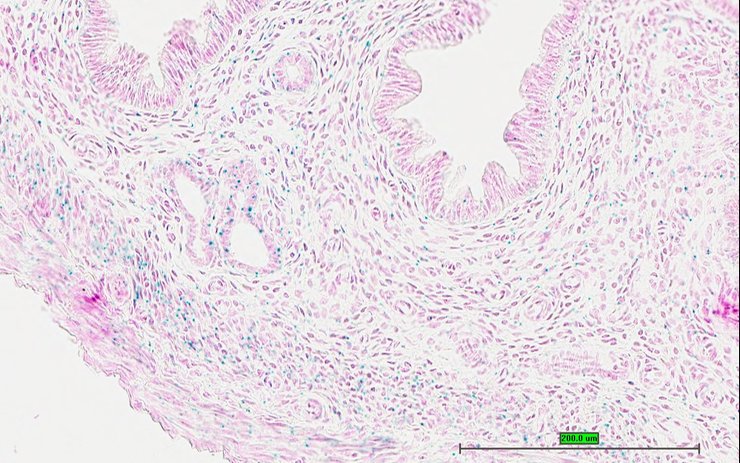

TS28: bladder Present UC Davis_1884165

Specimen UC Davis_1884166: postnatal adult; Sumo1tm1.1(KOMP)Vlcg/Sumo1+ (more )

Structure Level Pattern Image Note

TS28: bladder Present UC Davis_1884166

Specimen UC Davis_1884167: postnatal adult; Sumo1tm1.1(KOMP)Vlcg/Sumo1+ (more )

TS28: bladder Present UC Davis_1884167